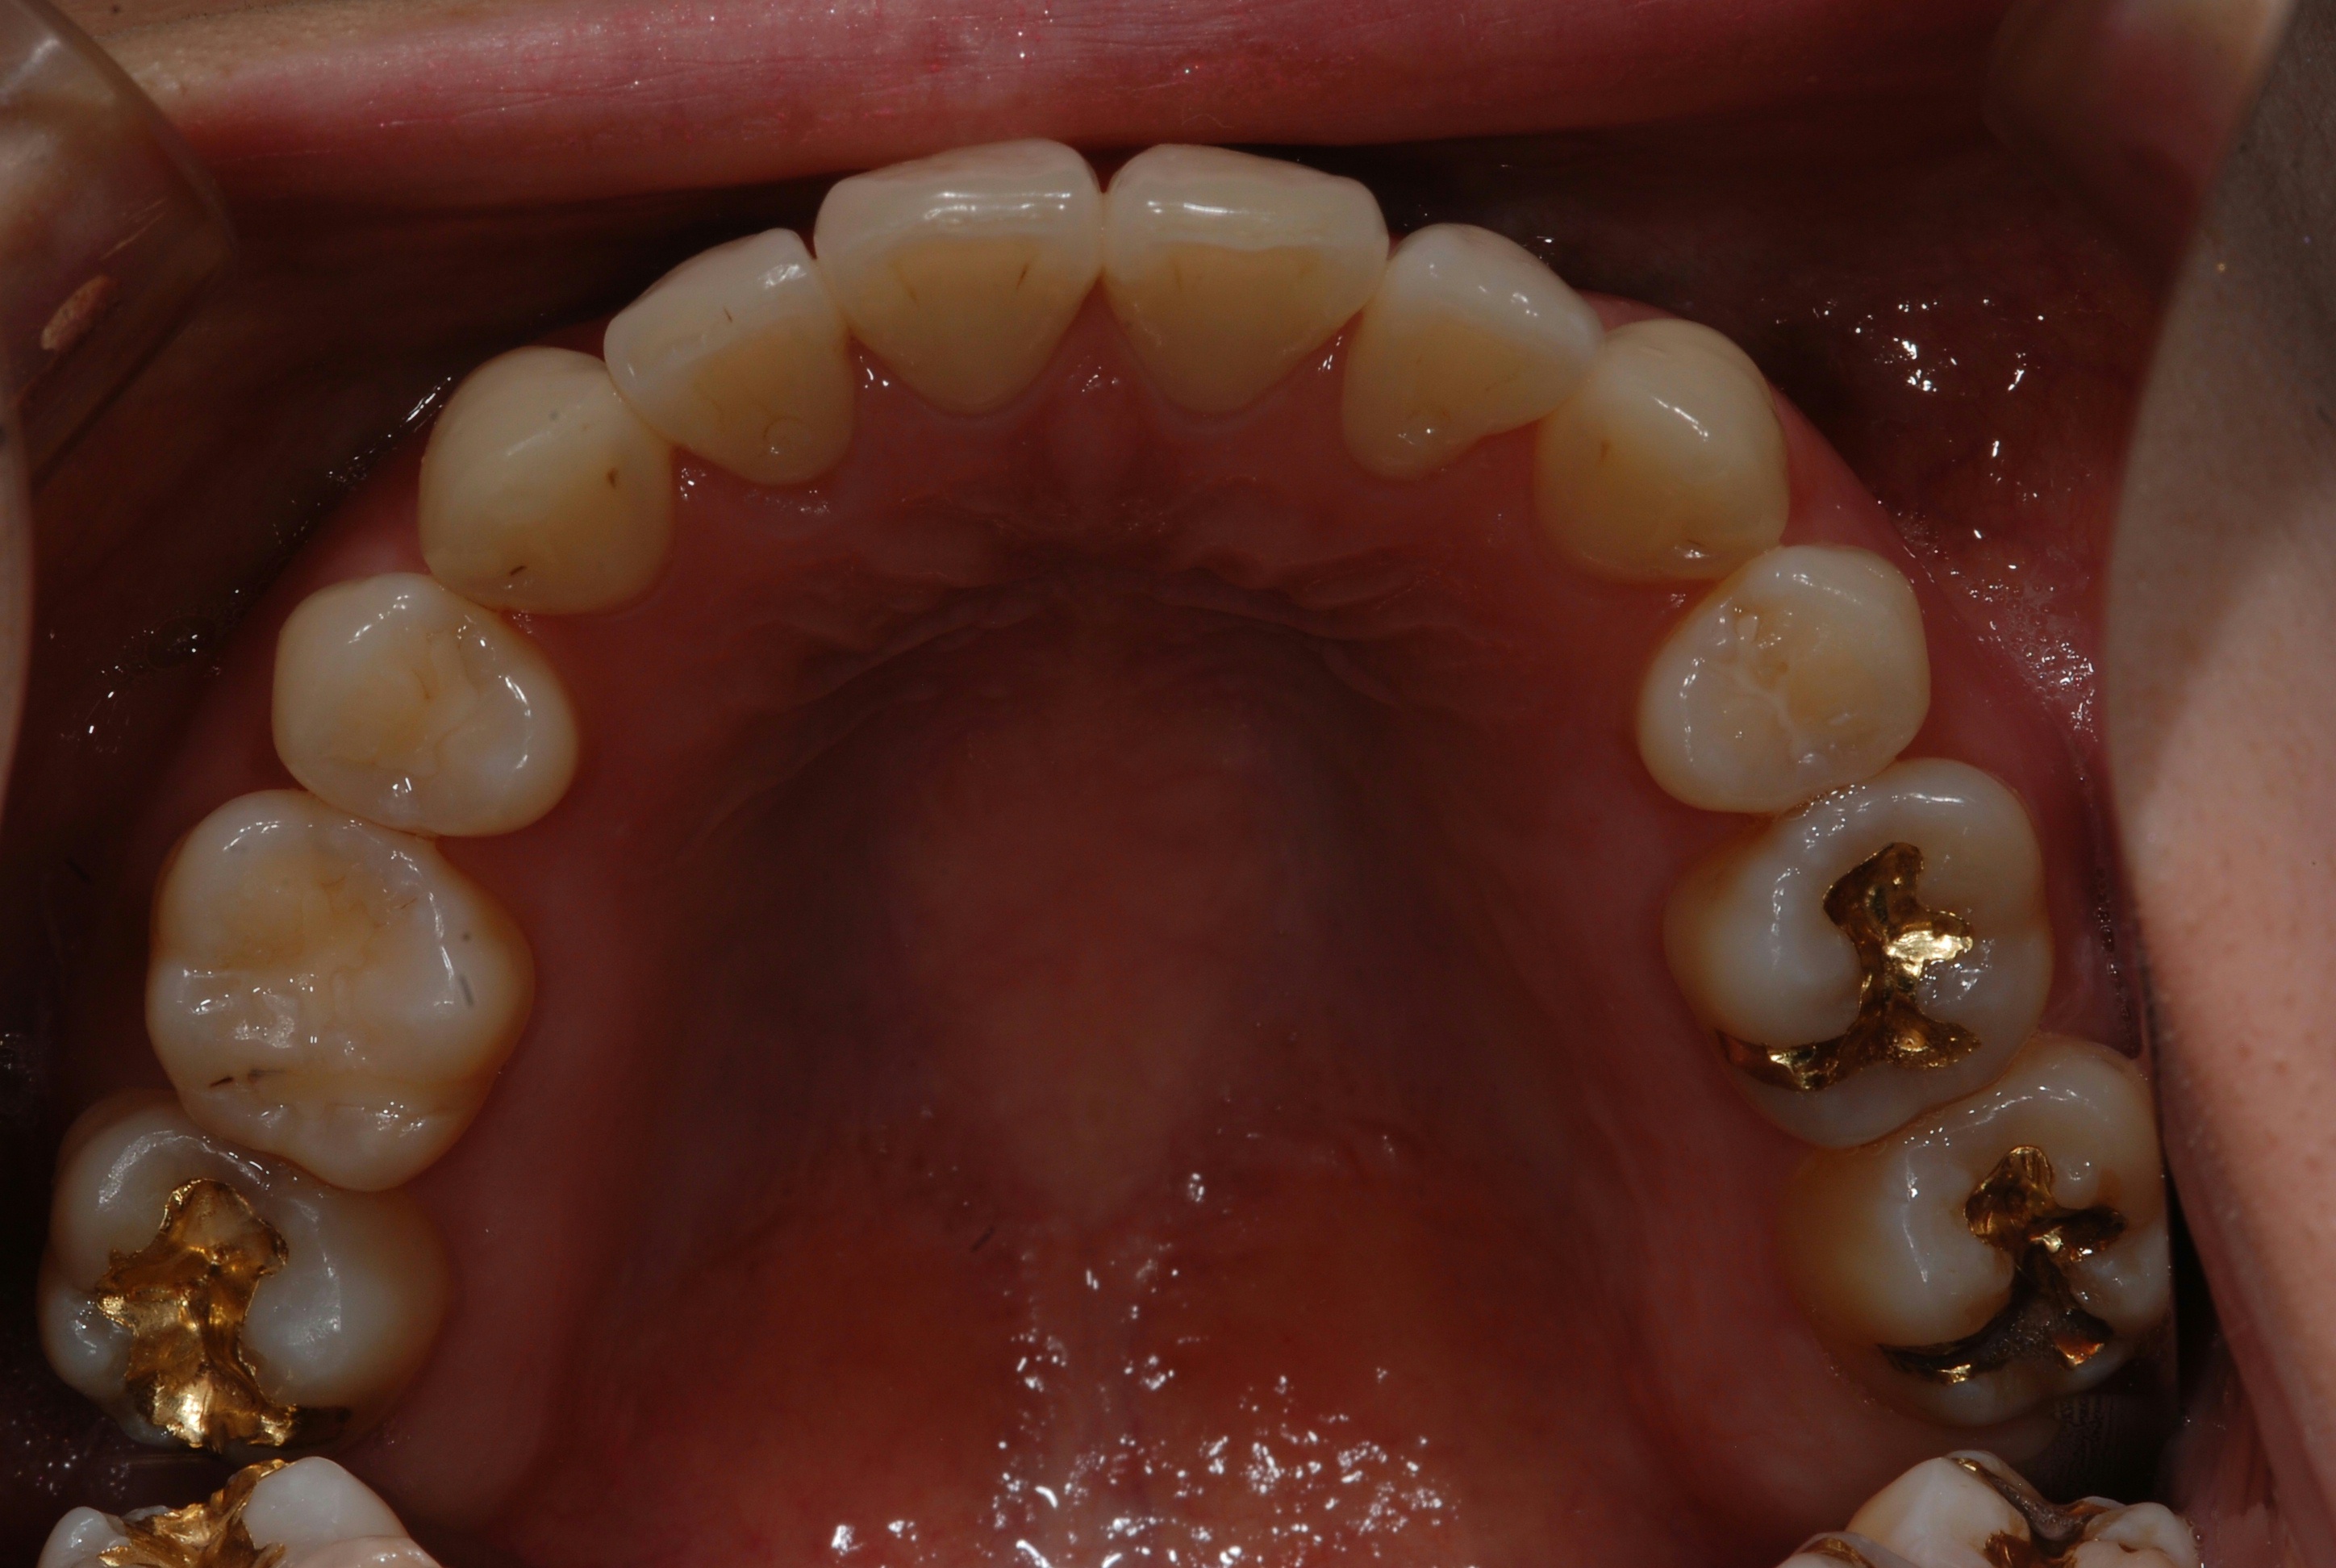

치료 후 사진입니다.